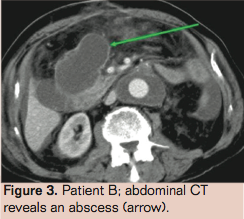

Patient B is a 73-year-old male with a history of subtotal colectomy (because of polyposis coli), transient ischemic attack, type 2 diabetes mellitus, coronary artery bypass grafting, and chronic obstructive pulmonary disease. Because of an asymptomatic juxtarenal aneurysm of the abdominal aorta with a maximum diameter of 7.1 cm, open aneurysm repair was performed with a Dacron tube prosthesis. Two days later he underwent a relaparotomy because of a fascia defect. Recovery was uneventful and he was discharged 2 weeks later. However, 3 days after discharge he returned to the emergency room with abdominal sepsis, a CRP of 238 mg/L and leukocyte count of 20.2 x109/L. Abdominal CT showed an intra-abdominal fluid collection in the right upper quadrant, left lateral, as well as fluid in and directly next to the surgically closed old

aneurysm sac (Figure 3). Both the collections in the right upper quadrant, left lateral and next to the old aneurysm sac were drained under CT guidance. Culture revealed a Corynebacterium jeikeium. We presumed that the prosthesis was colonized with the same microorganism. We considered him unfit for definitive surgical treatment because of his severe sepsis and hostile abdomen and therefore started the patient on vancomycin and rifampicin. During his admission, the patient developed several new intra-abdominal abscesses, which were all drained percutaneously.